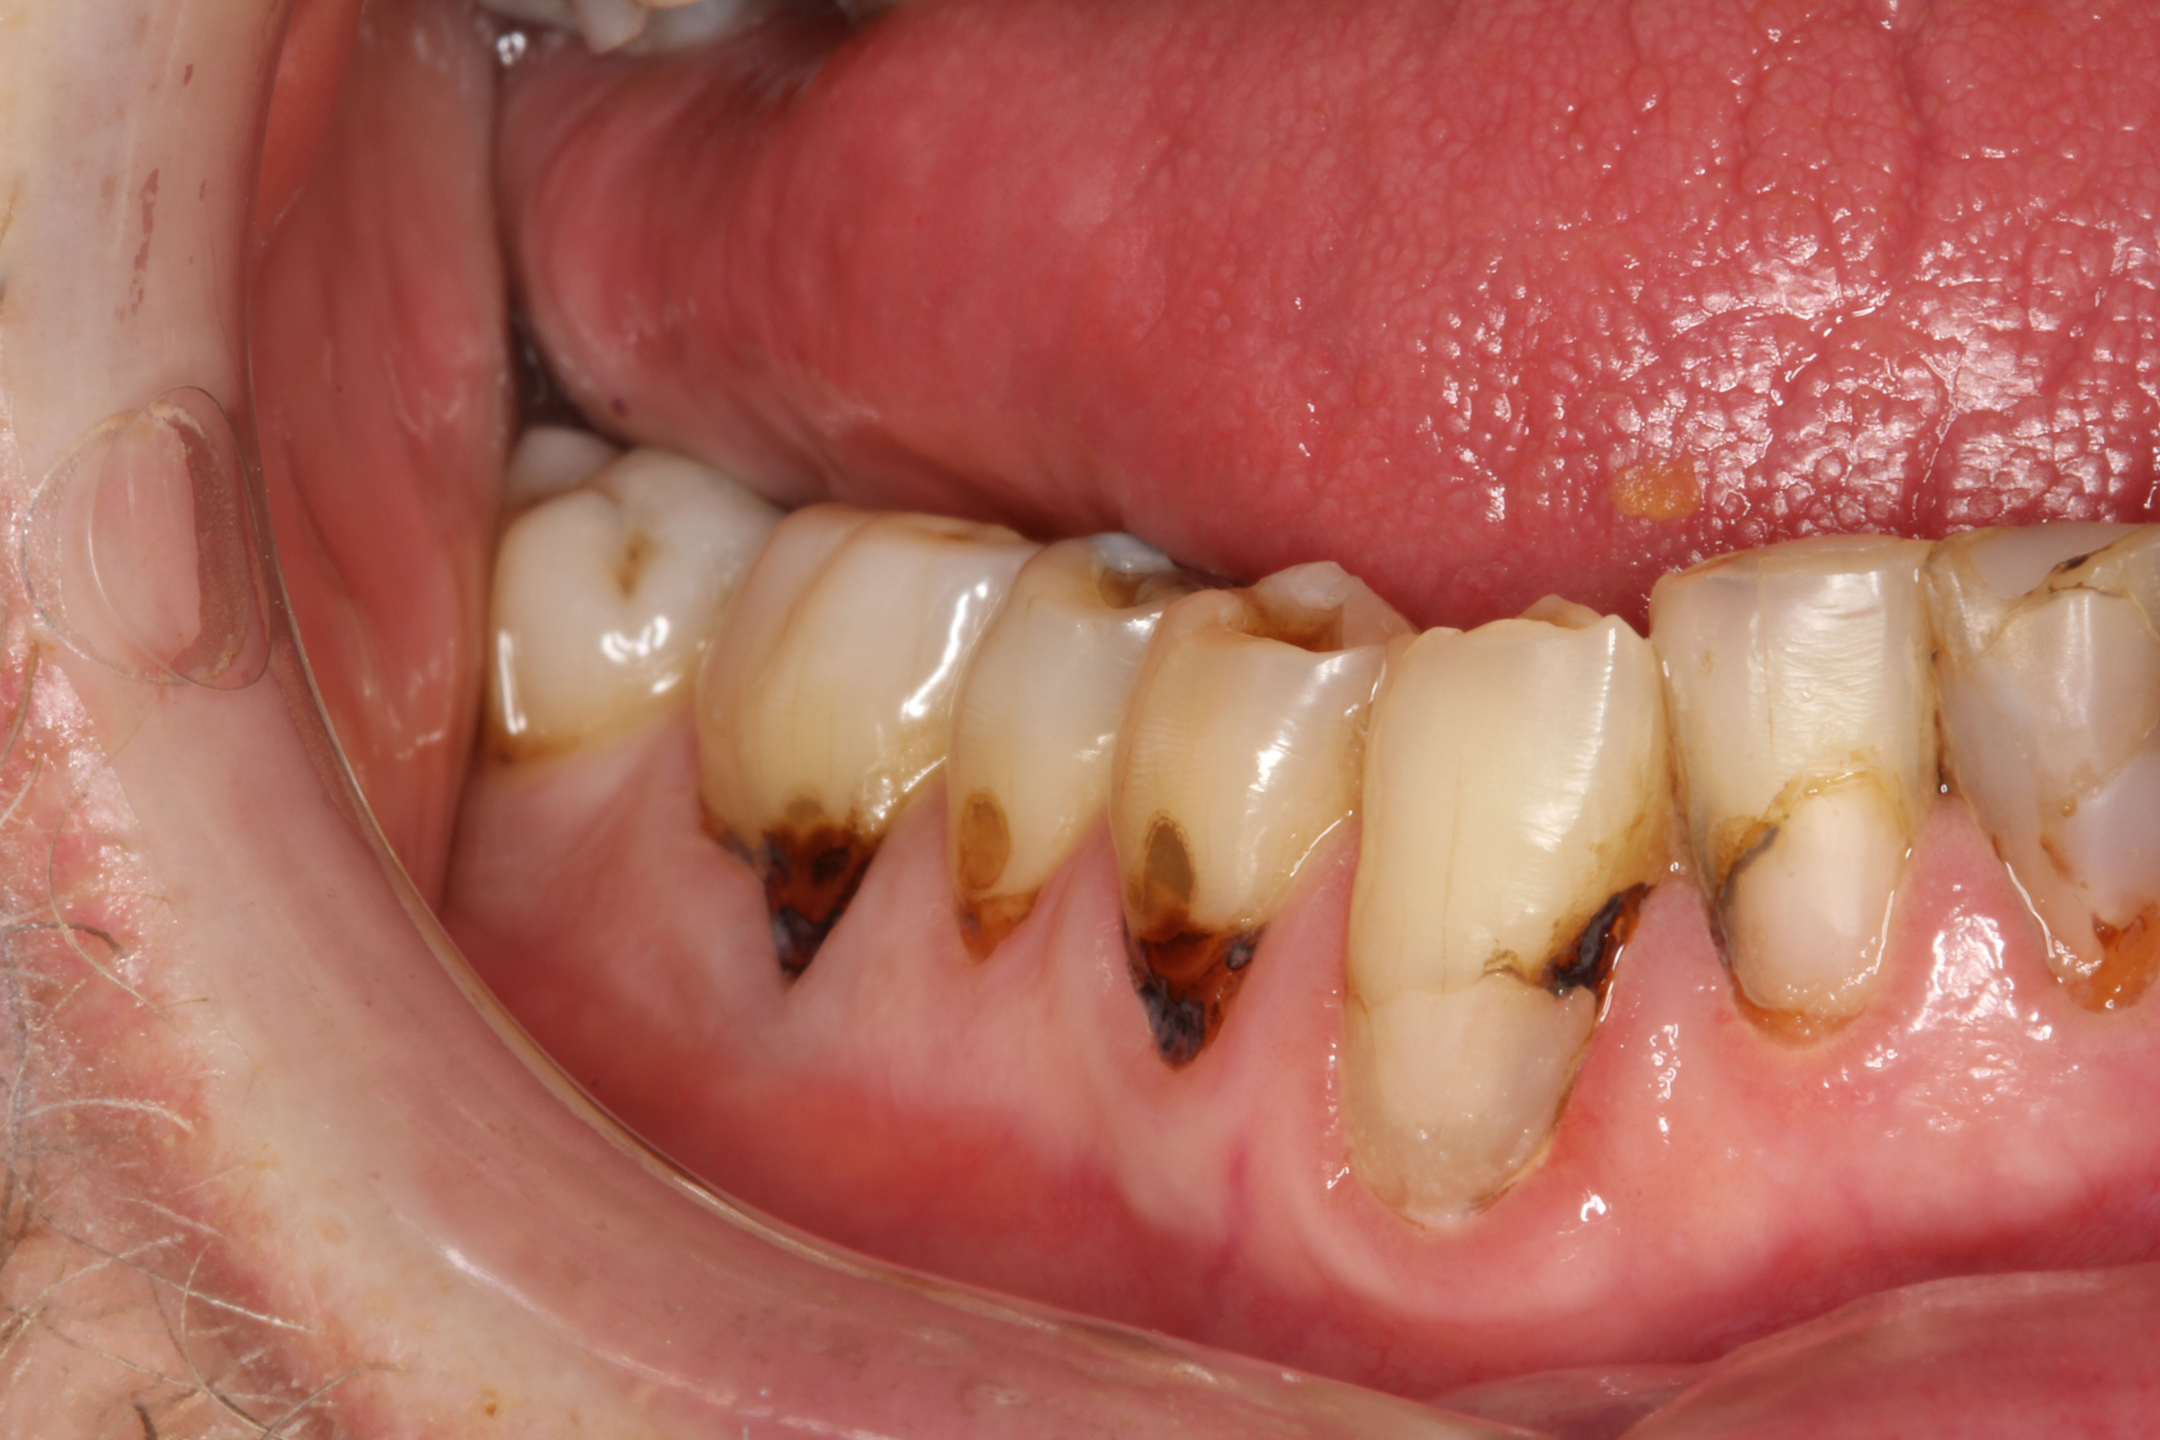

(15.) A 21-year-old patient returned for a second SDF/fluoride varnish treatment for cervical caries, 3 months after initial SDF application. The patient needed to delay restorative care for “personal reasons.”

Figure 15

(16.) A 21-year-old patient returned for a second SDF/fluoride varnish treatment for cervical caries, 3 months after initial SDF application. The patient needed to delay restorative care for “personal reasons.”

Figure 16